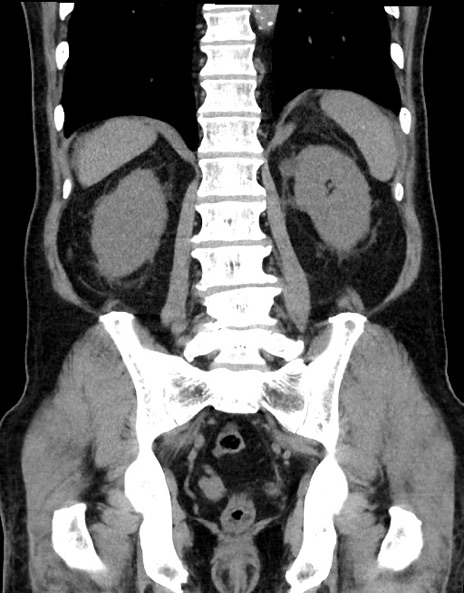

症例15(冠状断像)

【症例】70歳代男性

【主訴】腹痛

【現病歴】今朝から腹痛あり。全体的に痛い。特に左上の方。排ガスが今日はない。冷や汗が出る。

【既往歴】直腸癌術後

【身体所見】左側腹部〜上腹部に圧痛あり。腹膜刺激症状明らかなではない。軽度反跳痛。左下腹部に術後瘢痕あり。

【データ】WBC 7700、CRP 0.02